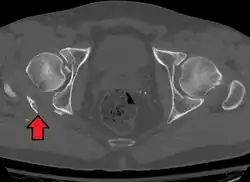

Axial CT image (viewed on bone windows) of a complex comminuted left acetabular fracture involving both anterior and posterior columns. -

-